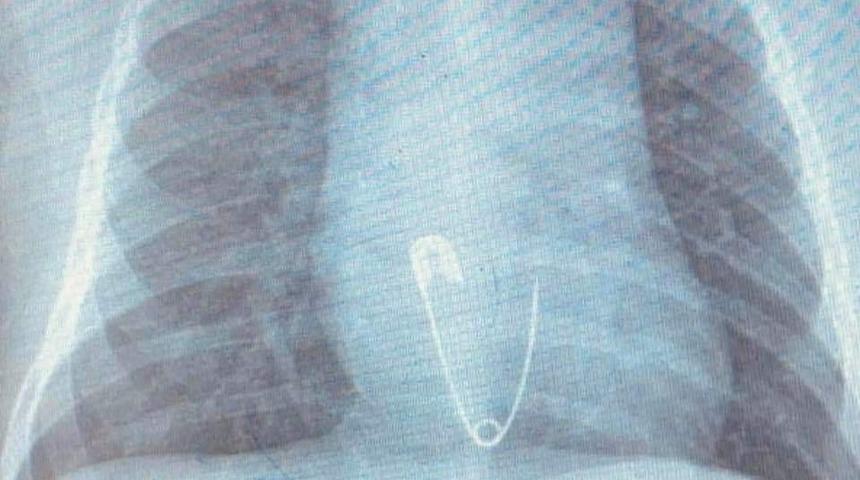

Hastanın Diyarbakır'dan Elazığ'a geldiğini belirten Prof. Dr. Yaşar Doğan, “Hastayı kabul ettik, 5 aylık bir hasta. Bize gelmeden önce üzerinde bulunan nazar boncuğunu çengelli iğne ile birlikte ağzına götürmüş. Aile de fark edince müdahale etmiş, ağzındaki nazar boncuğunu çıkarmış fakat o esnada çengelli iğne yemek borusuna kaçmış. Hasta geldiği zaman çektiğimiz röntgende çengelli iğne yemek borusunun alt kısmında takılı vaziyetteydi. Hastaya 15 dakikalık sedasyon altında işlem yapıldı, endoskopi ile parça çıkarıldı. Hasta şu anda gayet iyi. Biraz sonra da evlerine göndereceğiz” dedi.